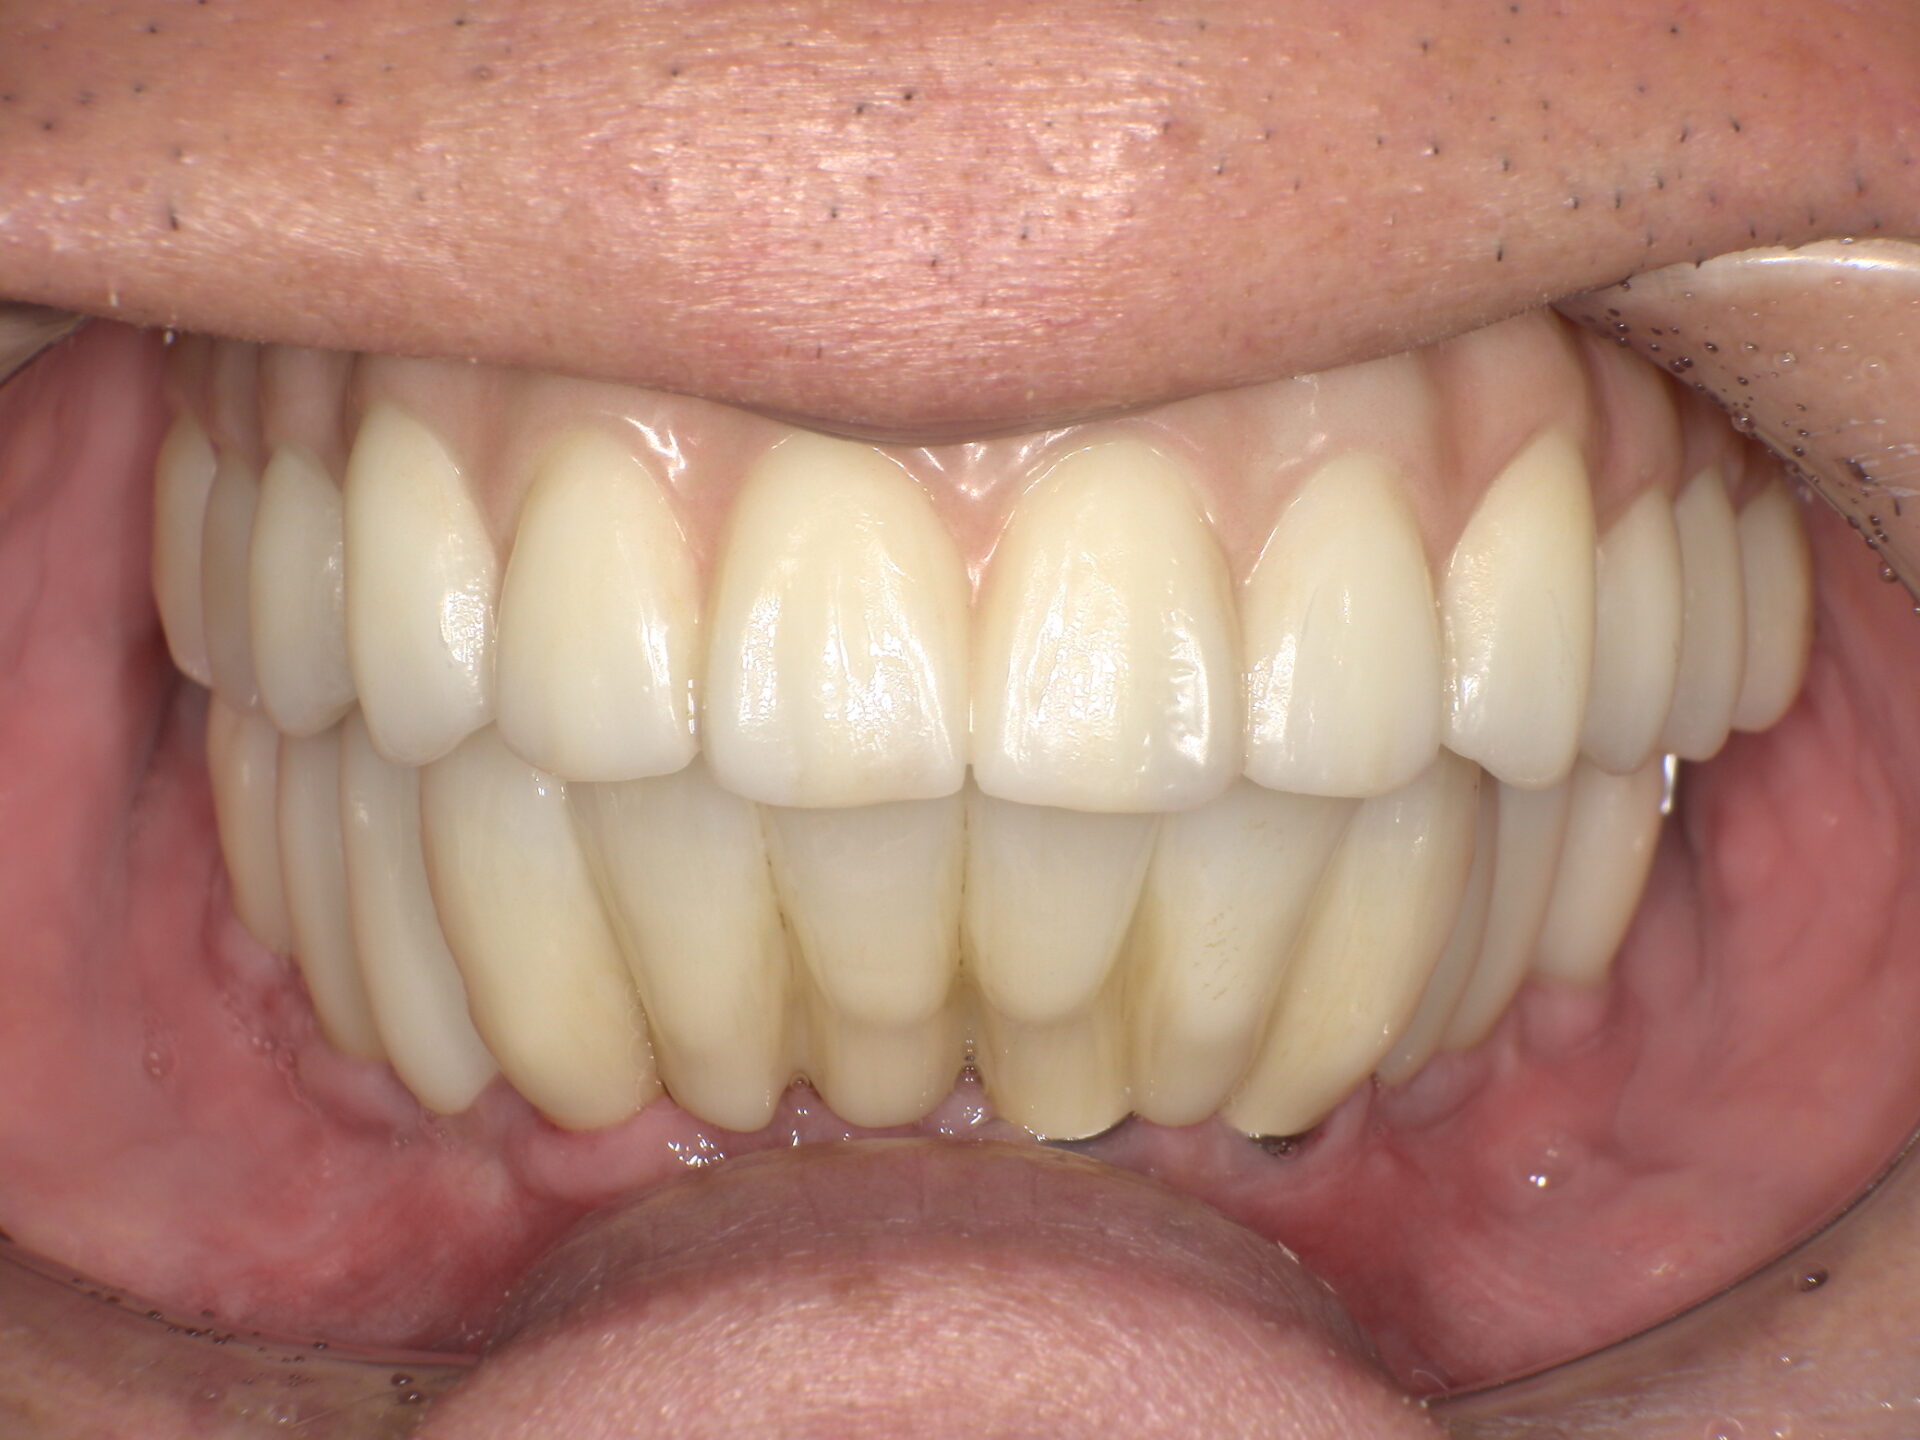

患者さんの年齢 60代 男性 症状 白い歯を入れて噛めるようにしてほしい 治療内容 インプラント治療(オールオン4) 費用 費用900万(税抜) 治療期間・回数 治療期間2年・通院回数12回 メリット なんでも噛める 見た目が綺麗になった デメリット・リスク 骨造成などで費用が増える場合がある - インプラント治療

before

after

患者さんの年齢 50代 男性 症状 何も噛めない 治療内容 インプラント治療(オールオン4) 費用 費用900万(税抜) 治療期間・回数 治療期間2年・通院回数12回 メリット なんでも噛めるようになる 見た目が綺麗 デメリット・リスク 骨造成などで費用が増える場合がある - インプラント治療